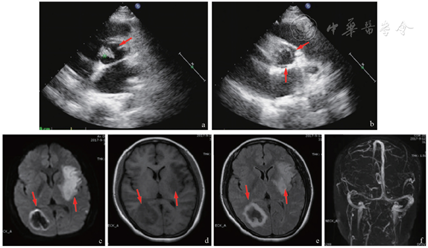

辅助检查:生化、免疫、血管炎相关、蛋白S、蛋白C未见异常;血常规:白细胞计数13.4×109/L,中性粒细胞百分比82.8%,血红蛋白浓度为74.0 g/L,血小板计数为404.0×109/L。心电图正常。经胸心脏彩色超声检查:(1)主动脉瓣轻度关闭不全;(2)左侧心功能测值射血分数、缩短分数正常范围。头部CT+头颈部CT血管成像(图1):(1)颅脑、颈部CT血管成像未见明显动脉硬化;(2)右侧枕叶脑出血;(3)左侧基底节-放射冠区低密度影。颅脑磁共振平扫+颅脑静脉成像(MRI+MRV,图2):(1)左侧额、颞、顶、岛叶及基底节、放射冠、半卵圆中心区急性梗死;(2)右侧枕叶脑出血;(3)颅脑静脉系统未见异常。